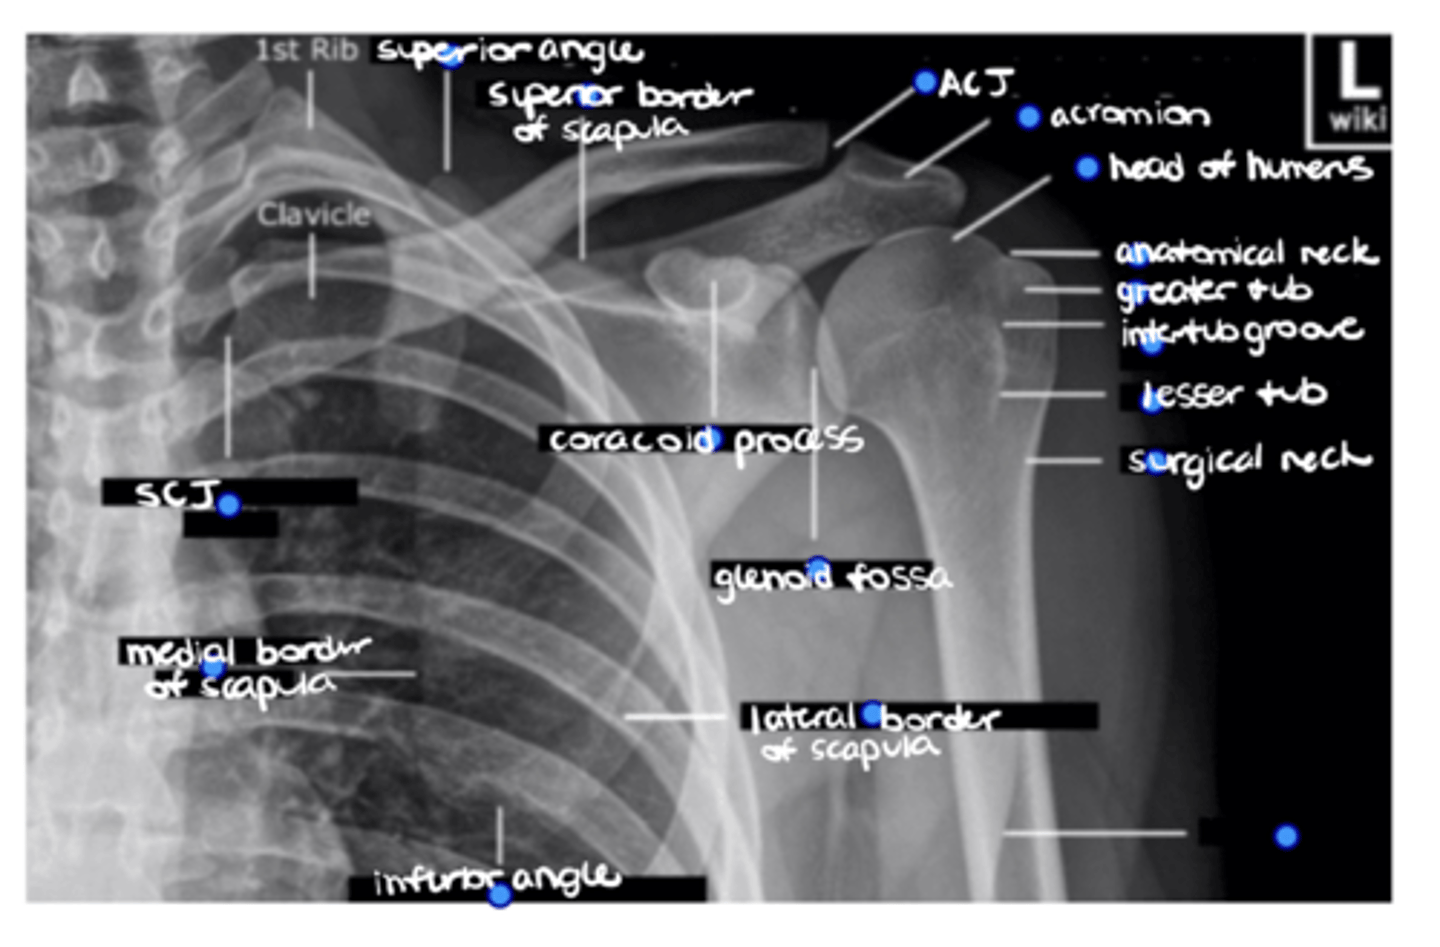

1. Head of humerus

2. Anatomical neck

3. Greater tuberosity

4. Intertubercular groove

5. Lesser tuberosity

6. Surgical neck

ID the 6 missing structures.

Shaft of the humerus